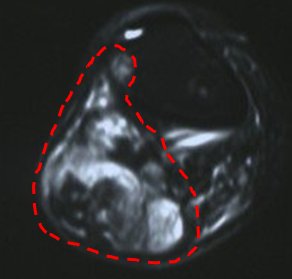

İyi huylu kemik tümörleri ise daha çok kemik kistleri, kıkırdak kökenli bazı tümörler yada dev hücreli kemik tümörü gibi bir takım lezyonlardır. Kistler basit olabileceği gibi kompleks de olabilir. Basit kemik kistleri daha çok çocuklarda görülür. En sık bölge omuz çevresi olmakla beraber her kemikte ortaya çıkabilir (resim-5). Basit kemik kistinin tedavisinde bazı durumlarda ameliyat gerekirken bazen de ameliyatsız tedavi uygulanabilir. Bunun için hastaya ameliyathane şartlarında kist içine enjeksiyon uygulanır ve bunu birkaç kez tekrarlamak gerekebilir (resim-6). Kompleks kist ile anlatılmak istenen ise “anevrizmal” kemik kistidir. Bunun tedavisi sadece cerrahi olup kist temizlendikten sonra içi bir takım özel maddelerle muamele edilmelidir. Oluşan boşluk kemik çimentosu yada kemik tozlarıyla doldurulur (resim-7). Anevrizmal kemik kisti basit kemik kistine göre daha saldırgan bir lezyon olup bazen kemiği tamamen ortadan kaldırabilir. Bunda nüks olasılığı da daha fazladır.